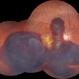

- SRNVM, CNVM, subretinal blood

- Colour fundus photograph of a 60 year old female with subretinal blood suggestive of subretinal neovascular membrane